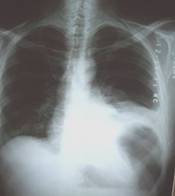

Existía un área de necrosis en curvatura mayor que se le realizó exéresis para examen histopatológico revelando carcinoma gástrico difuso tipo linitis plástica (figura 3 y figura 4).

Fig. 3 y Fig 4. Carcinoma gástrico difuso tipo linitis plástica.

Estudio histopatológico: Carcinoma gástrico difuso tipo linitis plástica. Micro: células discohesivas que infiltran a través de la pared gástrica como células individuales embebidas en un estroma desmoplástico.